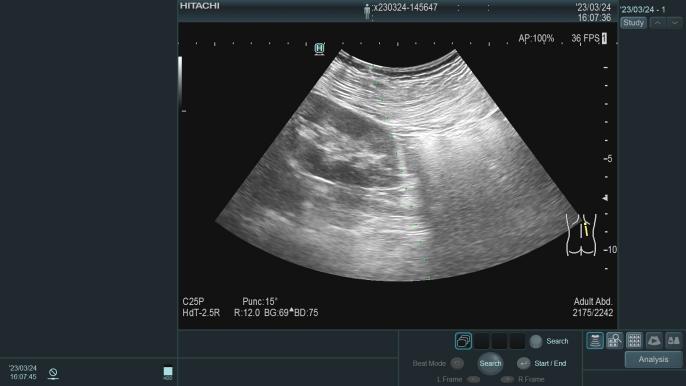

3.B超引导下肾穿刺活检术、腹透管植入术以及经皮内瘘血管形成术(PTA)、动静脉内瘘成形术以及透析血管通路的并发症诊治;

在广西较早独立编制的肾脏病专业科室,1995年开始应用超声引导下经皮肾穿刺活检术,协助诊断治疗各类肾脏疾病,积累丰富临床经验,如:急性肾小球肾炎、慢性肾小球肾炎、急性肾损伤、慢性肾衰竭、肾病综合征、IgA肾病、狼疮性肾炎、ANCA相关性小血管炎、糖尿病肾病、高血压肾病等疾病的诊断及治疗。

肾穿刺活检术